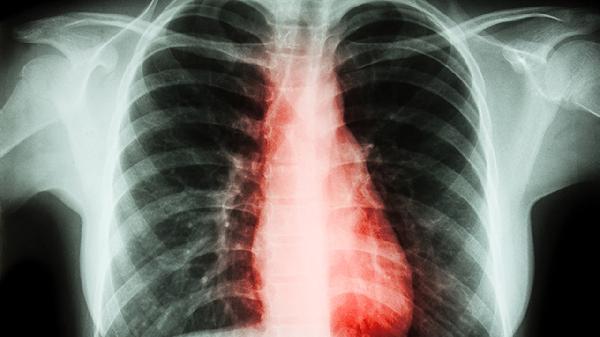

后胸椎疼痛是什么原因

后胸椎疼痛可能與肌肉勞損、骨質(zhì)疏松、胸椎間盤(pán)突出、強(qiáng)直性脊柱炎、胸椎腫瘤等因素有關(guān)。建議及時(shí)就醫(yī),明確病因后遵醫(yī)囑治療。